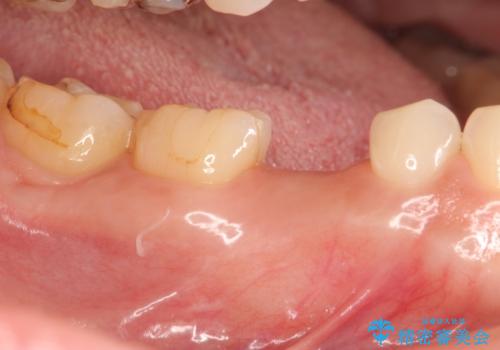

- 大人になっても残っていた乳歯が噛むと痛くなり、治療を求めて来院されました。

残す手段を検討しましたが大きな虫歯・根尖病変の存在し、大きく歯ぐきも腫れ炎症も強く認められる状態を改善するため抜歯を行いインプラントによる咬合機能回復を計画します。